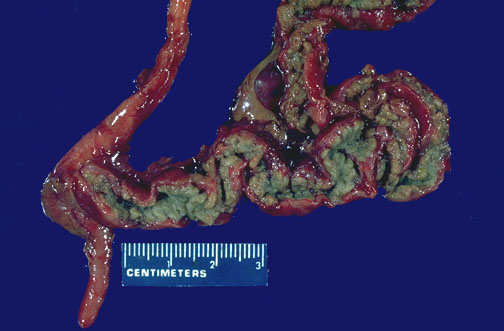

The small intestine is shown here opened to reveal the greenish, inspissated contents. The colon and appendix beyond the ileocecal valve at the left are normal.